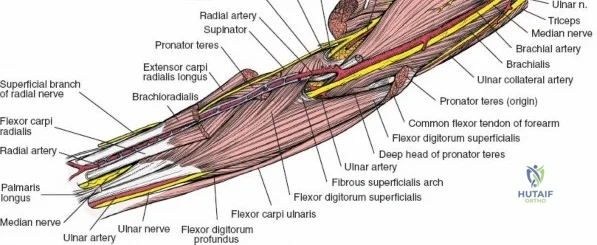

The anterior approach to the radius is an elegant example of utilizing true internervous planes to achieve deep exposure without denervating musculature. Distally, the internervous plane lies between the brachioradialis muscle (innervated by the radial nerve) and the flexor carpi radialis muscle (innervated by the median nerve). Proximally, the plane transitions to lie between the brachioradialis (radial nerve) and the pronator teres muscle (median nerve). Exploiting this plane allows the surgeon to mobilize the entire lateral muscular compartment (the "mobile wad" comprising the brachioradialis, extensor carpi radialis longus, and extensor carpi radialis brevis) away from the anterior flexor compartment.

Vascular Anatomy and the Recurrent Radial Leash

The radial artery runs distally through the forearm, initially lying deep to the brachioradialis muscle before becoming more superficial in the distal third. Just distal to the elbow joint, the radial artery gives off a complex network of vessels known as the recurrent radial artery leash (the "leash of Henry"). These vessels branch laterally to supply the brachioradialis and the mobile wad. To successfully mobilize the brachioradialis laterally and access the proximal radius, this entire leash of vessels must be meticulously isolated, ligated, and divided. Failure to do so will tether the brachioradialis, prevent adequate exposure, and risk severe postoperative hematoma from avulsed vessels.

Managing the Radial Artery and Recurrent Leash

As the brachioradialis is retracted laterally, the radial artery and its venae comitantes are exposed lying deep in the middle part of the forearm, closely related to the medial edge of the wound. Begin dissection distally and work proximally. Just below the elbow joint, the radial artery gives off the recurrent radial artery and a leash of muscular branches that dive laterally into the brachioradialis.

This leash must be meticulously managed. Take time to isolate, ligate, and divide these vessels. Do not attempt to use electrocautery alone on the larger branches, and absolutely avoid blunt avulsion. Avulsion of these vessels from the main radial artery is a potent cause of difficult-to-control intraoperative bleeding and severe postoperative hematoma. Once the leash is divided, the brachioradialis can be fully mobilized laterally, exposing the deep muscular layer.